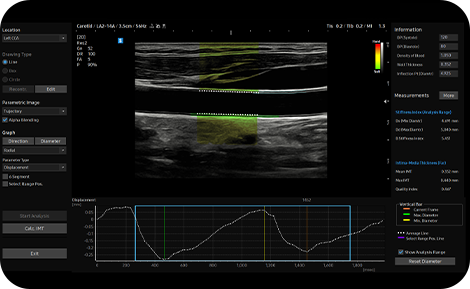

ArterialAnalysis™ detecta los cambios funcionales de los vasos, proporcionando valores de medición como la rigidez, el grosor de la íntima-media y la velocidad de la onda de pulso de la arteria carótida común.

Mida el IMT en un solo clic

AutoIMT+™ es una herramienta de cribado para analizar el riesgo potencial de enfermedad cardiovascular de un paciente. Permite medir fácilmente el grosor de la íntima-media de la pared anterior y posterior de la carótida común con sólo pulsar un botón.